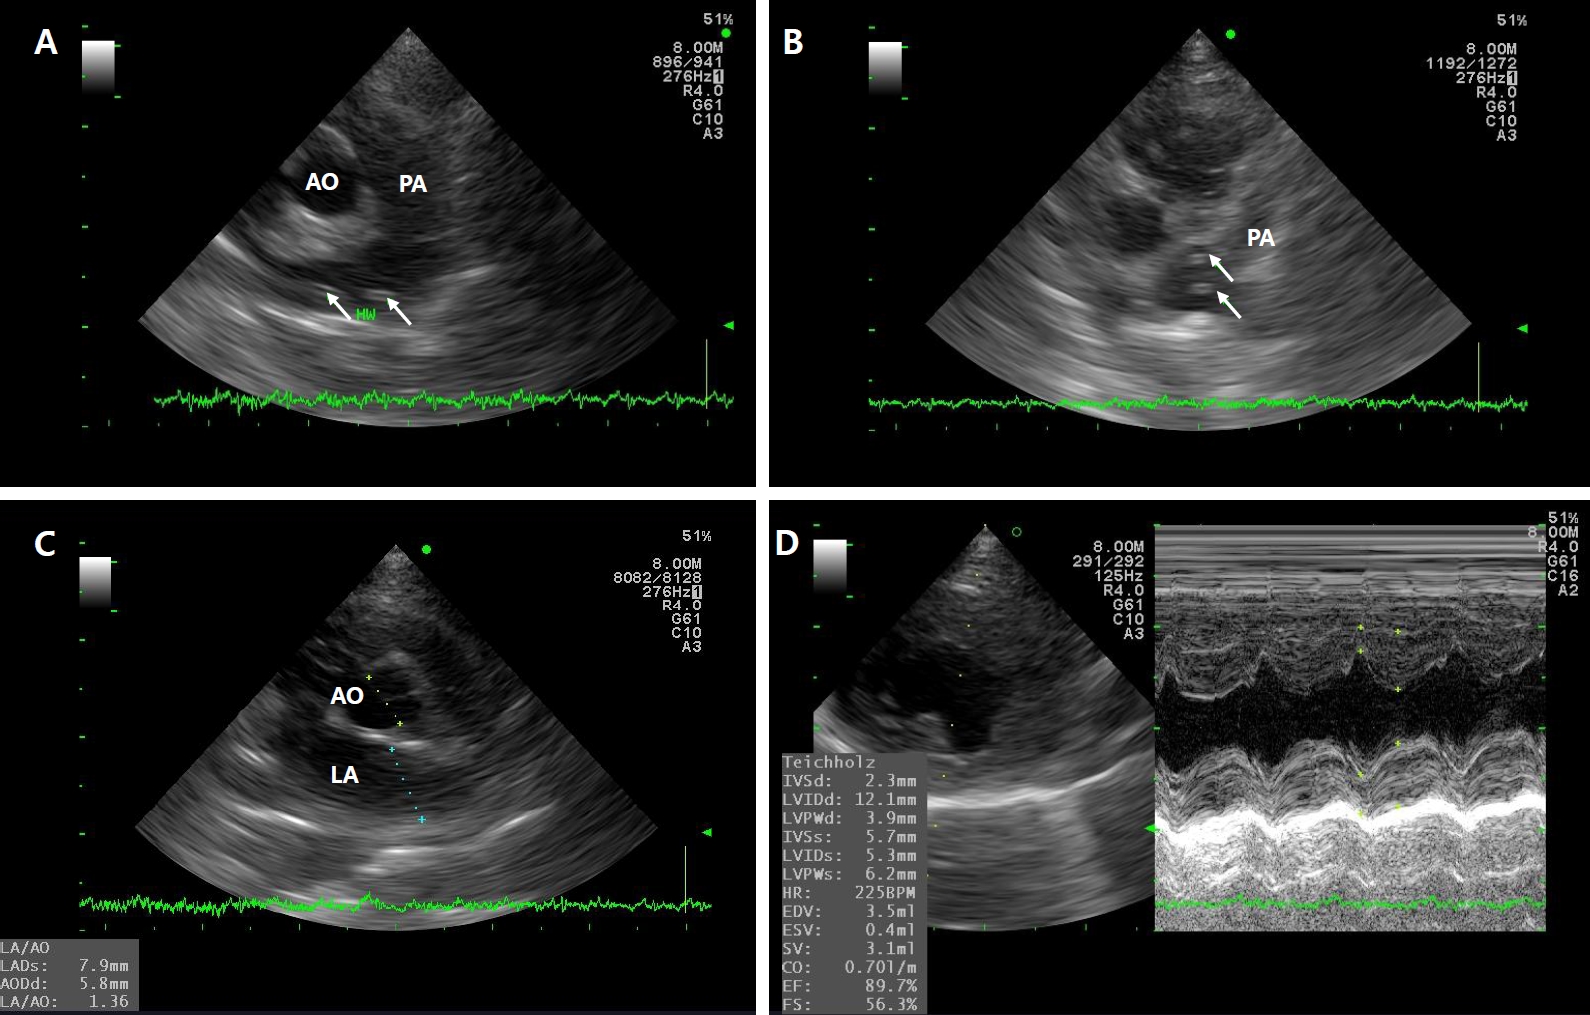

Fig. 1.

Thoracic radiographs of Case 1. Day 1: (A) ventrodorsal view and (B) right lateral view. Pulmonary artery enlargement extending to the right caudal lung lobe is evident in the dorsoventral projection. Additionally, interstitial infiltration is present in the lung field, with multiple fissure lines observed. Day 5: (C) ventrodorsal view and (D) right lateral view. Compared with the findings on Day 1, pulmonary infiltration decreased over the 5-day period.

The cat was treated with oxygen supplementation, maintenance fluid therapy, prednisone [1 mg/kg orally (PO) twice daily (BID)], doxycycline (5 mg/kg PO BID), acetylcysteine (10 mg/kg PO BID), pheniramine (1 mg/kg PO BID), and metronidazole (10 mg/kg intravenously BID). Daily thoracic radiographs were obtained to monitor lung condition (Fig. 1). On hospitalization day 5, thoracic radiographs showed normalization of pulmonary fields. At discharge, prednisone (1 mg/kg PO BID), doxycycline (5 mg/kg PO BID), acetylcysteine (10 mg/kg PO BID), and pheniramine (1 mg/kg PO BID) were prescribed for an additional week to manage HARD [11]. Revolution (selamectin, Zoetis) was applied topically once a month as a preventive macrocyclic lactone to avoid reinfection and target potential immature stages [12]. Thoracic radiographs showed no significant changes upon reevaluation after 1 week. The same medications were continued, except prednisone, which was tapered to 0.5 mg/kg PO every other day for 2 weeks. Subsequent follow-up radiographs revealed no significant changes, and a medication-free period was initiated.

Fig. 1. Thoracic radiographs of Case 1. Day 1: (A) ventrodorsal view and (B) right lateral view. Pulmonary artery enlargement extending to the right caudal lung lobe is evident in the dorsoventral projection. Additionally, interstitial infiltration is present in the lung field, with multiple fissure lines observed. Day 5: (C) ventrodorsal view and (D) right lateral view. Compared with the findings on Day 1, pulmonary infiltration decreased over the 5-day period.